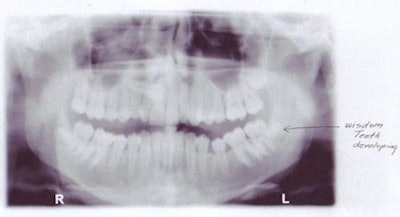

| Left, bitewing shows the large pulp typical of a 9-year-old. Right, bitewing of a 16-year-old shows a smaller pulp. | |